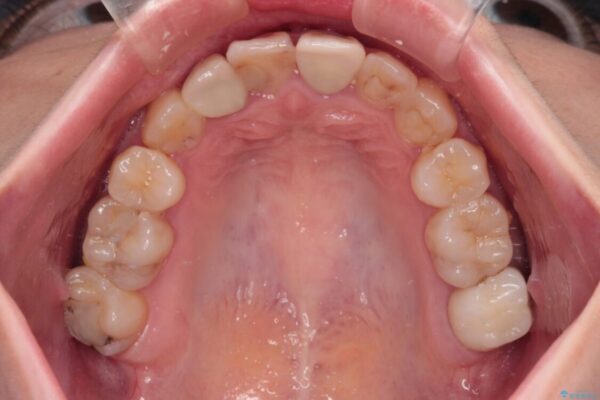

治療前

• 虫歯治療ついでに歯並びの後戻りを改善 インビザラインによる矯正治療 治療前画像

奥歯が痛いとのことで来院された患者様です。

治療計画

上顎親知らず周辺の炎症と、神経組織の失活した歯の炎症による痛みが認められたため、親知らずの抜歯と根管治療を行いました。

根管治療を行った歯はクラウンによる補綴治療が必要となりますが、高校生の頃に行った矯正治療の後戻りも気になるとのことで、補綴治療を行う前に矯正治療を行うこととしました。

後戻りは軽度であり、インビザラインにて歯列を整え、その後にオールセラミッククラウンにて補綴治療を行うこととしました。